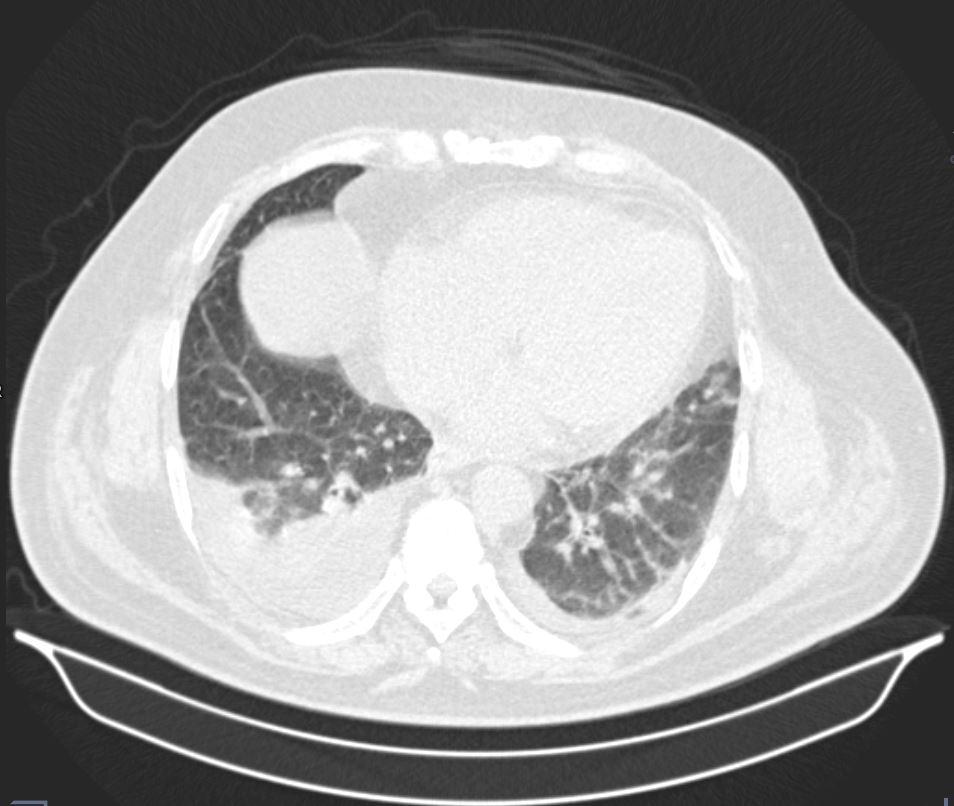

Case of the Week 24 2017 *50-year-old male with shortness of breath. What is the most likely diagnosis? Answer Answer: Pleural effusion and passive atelectasis Kategori:Cases Önceki yazı Case of the Week 27 2017 Sonraki yazı Case of the Week 25 2017